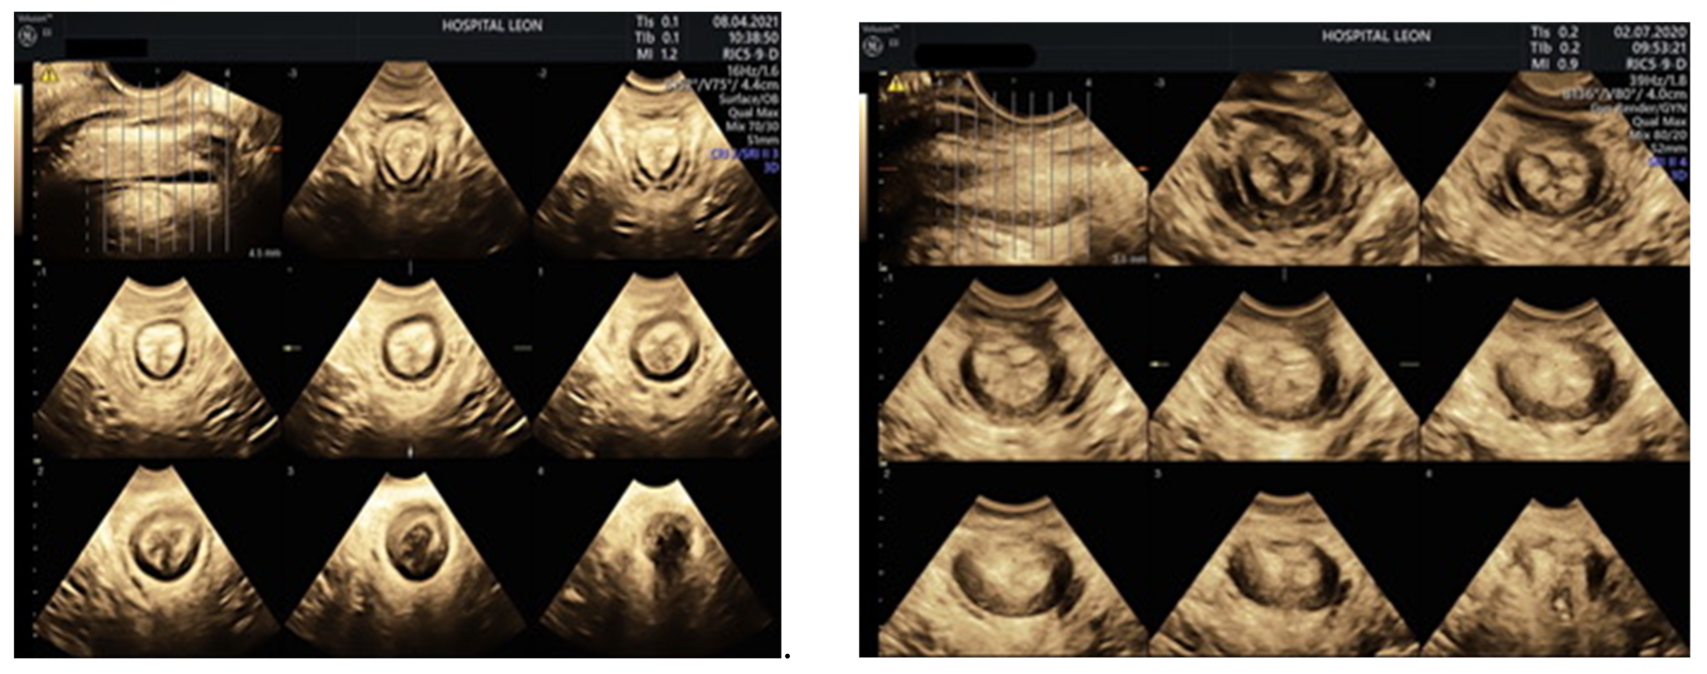

2.1.2. Transperineal Ultrasound (TPUS)

- García-Mejido, J.A.; Palomino, L.G.; Palacín, A.F.; Sainz-Bueno, J.A. Applicability of 3/4D transperineal ultrasound for the diagnosis of anal sphincter injury during the immediate postpartum. Cir. Cir. (Engl. Ed.) 2017, 85, 80–86. [Google Scholar] [CrossRef]